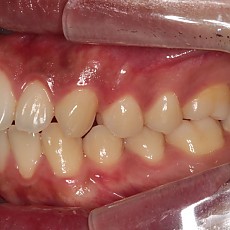

시술전후사진 12 페이지

Total 189건 12 페이지